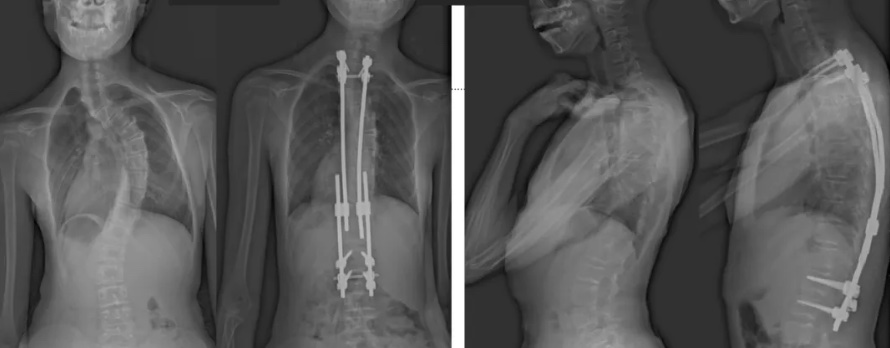

白瑪的正位術前、術后對比圖(左側);側位術前、術后對比圖(右側)

白瑪今年10歲,正在讀小學。媽媽發現,白瑪經常歪著肩膀,在反復提醒“站直了,別歪著”后,情況也沒有改善。近半年來,白瑪的右側肩胛骨逐漸向后凸出。到醫院檢查后發現,白瑪的胸椎存在明顯的側凸畸形,是早發型特發性脊柱側凸。由于側凸較為嚴重,已經失去了支具治療的機會。小白瑪才10歲,隨著身體的不斷成長,她的脊柱會越來越彎,肩膀會越來傾斜。這不僅影響體態和外觀,也可能限制心、肺等內臟器官的發育,導致心肺功能下降、肢體活動不便,出現癱瘓,甚至死亡。對于白瑪這種情況,只能利用手術治療來矯正脊柱、阻止骨骼畸形進展。

術后第二天,白瑪就下地活動了。媽媽驚喜地發現,白瑪一下子“長高”了近十厘米,重新抬起了頭,挺直了脊梁,肩膀也不歪了,可謂“脫胎換骨”。媽媽激動地錄制了一段白瑪走路的身影,把喜悅分享給全家。白瑪的術后檢查也提示,手術成功,恢復良好。